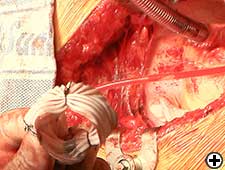

- Cross clamp, cardioplegia, aortotomy, and excision of aortic valve as routine.

- Divide aorta by extending aortotomy.

- Dissect under surface of aorta: proximally to the root and distally to the under surface of arch.

- Replace aortic valve as per routine.

- Distal part of aorta passed back through the folded Dacron graft.

- Aorta re-anastomosed with 4.0 continuous sutures.

- Cover the aortic cannulation site with Dacron sleeve by slightly stretching over it (Figure 7).